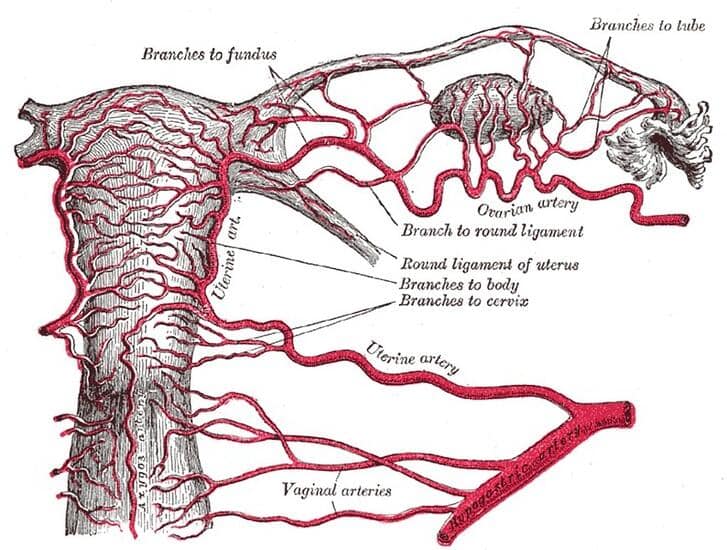

Al llegar al cuello del útero a cada lado, las arterias uterinas desprenden una rama ascendente, que discurre en forma superior a lo largo del útero, y una rama descendente que discurre en forma inferior hacia la vagina.

A nivel de la unión cervico-uterina, la arteria uterina se divide en una rama ascendente y otra descendente.

Pasa de manera superior y tortuosa a lo largo de la pared lateral del cuerpo del útero hacia la trompa uterina. A lo largo de su curso, la rama ascendente desprende múltiples pequeñas ramas que entran en la pared lateral del útero, y se ramifica en el miometrio del útero en las arterias helicina, arcada, radial, espiral y basal.

La rama ascendente continúa en forma superior hasta llegar a la trompa uterina en la región del hilio ovárico, donde se divide en ramas ováricas y tubáricas.

Estas ramas se anastomosan con las ramas ováricas y tubáricas de la arteria ovárica. En resumen, la rama ascendente abastece el margen lateral del útero, la porción media del ovario y el tubo uterino.

Rama descendente

Pasa inferiormente hacia la vagina. Esta rama vaginal se anastomosa con ramas de la arteria vaginal formando arterias longitudinales medianas y arterias ácigos de la vagina, que descienden a lo largo de la pared anterior y posterior de la vagina.

A lo largo de su curso, la rama descendente irriga el cuello uterino y la vagina.